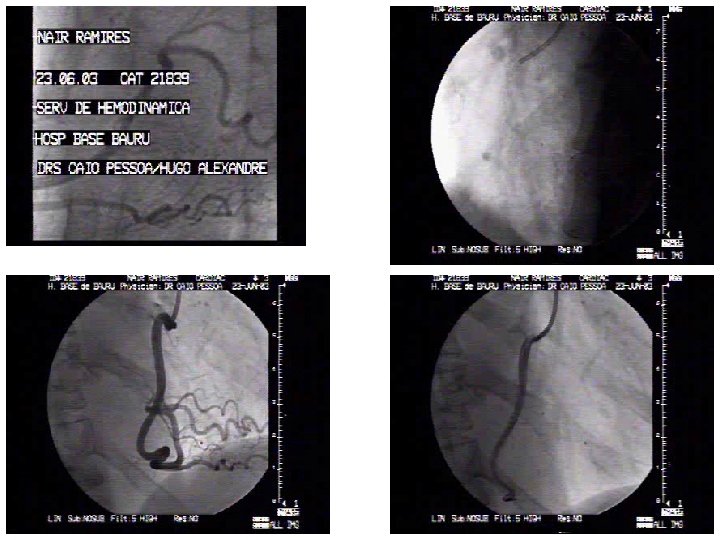

Nair C. Rodrigues Sexo - feminino Idade – 63 anos HAS Hipercolesterolemia Unidade Coronária 10/02/2003 IAM não Q - anterior

Viabilidade? Estenose residual é limiante de fluxo? Um ou mais vasos? Risco de novo evento?